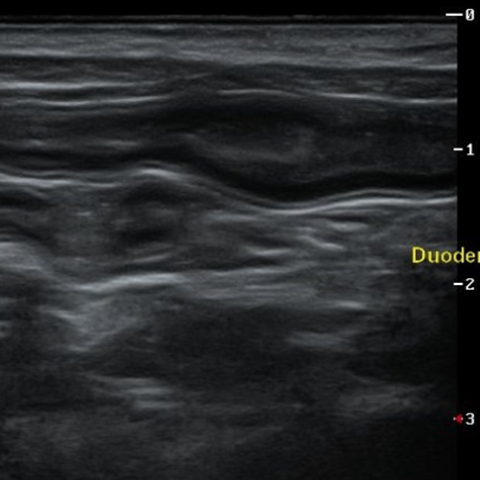

°í¾çÀÌ ¼¼µ¿ÀÌ¿°(Triaditis)

°í¾çÀÌ¿¡°Ô¼­ ²Ï ÈçÇÏÁö¸¸ Áø´ÜÀÌ ³ª¿ÔÀ» ¶§ º¸È£ÀںеéÀÌ ¸¹ÀÌ »ý¼ÒÇØ ÇϽô ÁúȯÀä, °£´ÜÈ÷ ¸»ÇØ ´ã°ü°£¿°, ÃéÀå¿°, Àå¿°(¿°Áõ¼ºÀåÁúȯ)ÀÌ µ¿½Ã¿¡ ¹ß»ýÇÏ°Ô µÈ »óÅÂÀÔ´Ï´Ù. ±¸Åä, ¼³»ç, ±â·Â ¹× ½Ä¿åÀúÇÏ °°Àº Áõ»óÀÌ ³ªÅ¸³ª°í ½ÉÇÑ °æ¿ì Ȳ´Þ°ú ºóÇ÷±îÁö ³ªÅ¸³¯ ¼ö ÀÖ´Â ÁßÁõ ÁúȯÀä, °í¾çÀÌ´Â ³»ºÎ Àå±âÀÇ ÇØºÎÇÐÀû ±¸Á¶ »ó ´ã°ü°ú ÃéÀå°üÀÌ ½ÊÀÌÁöÀå¿¡¼­ ÇÕÃÄÁö°Ô µÇ´Âµ¥, ÀÌ·Î ÀÎÇØ °£À̳ª ÃéÀå, ¼ÒÀå ¾î´À ÇÑ °÷¿¡ ¿°ÁõÀÌ »ý°Üµµ °¡±î¿î ÁÖº¯ Àå±â¿¡±îÁö ÀÌȯ µÇ¾î Àü½ÅÀûÀÎ ÁúȯÀ» ÀÏÀ¸Å°°Ô µË´Ï´Ù.

º¸Åë ±¸Åä, ¼³»ç, ±â·Â ¹× ½Ä¿åÀúÇÏ »óÅ·Π³»¿øÇÏ¿© °£ºÎÀü, Ȳ´Þ, ºóÇ÷±îÁö È®ÀεǴ °æ¿ì°¡ ¸¹Àºµ¥, ÀÌ·± »óÅ¿¡¼­´Â ÀÏÁ¤ ±â°£ ÀÌ»ó ÀÔ¿ø ÈÄ ¼ö¾×°ú ¾à¹° Ä¡·á°¡ ÇÊ¿äÇÕ´Ï´Ù. Áõ»óÀÌ °³¼±µÇÁö ¾Ê°í Ȳ´Þ°ú ºóÇ÷ÀÌ ¾ÇÈ­µÉ °æ¿ì »ç¸Á¿¡±îÁö À̸¦ ¼ö Àֱ⠶§¹®¿¡ °¡´ÉÇÑÇÑ ºü¸¥ ½ÃÀϳ»¿¡ °ø°ÝÀûÀÎ Ä¡·á¸¦ ÇØ¾ß ÇÕ´Ï´Ù.

¸ðµç ÁúȯÀÌ ±×·¸°ÚÁö¸¸, ¼¼µ¿ÀÌ¿°µµ Ãʱ⿡ ÀûÀýÇÑ Ä¡·á¸¦ ¹Þ´Â´Ù¸é ÃæºÐÈ÷ ȸº¹µÉ ¼ö ÀÖ½À´Ï´Ù. ÇÏÁö¸¸ ÁúȯÀÌ ÀÌ¹Ì ¸¹ÀÌ ÁøÇàµÈ ÈÄ¿¡ Ä¡·á¸¦ ½ÃÀÛÇϰųª, Á¦´ë·Î µÈ Ä¡·á°¡ ÀÌ·ç¾îÁöÁö ¾Ê´Â´Ù¸é ¾à¹°¿¡ ´ëÇÑ Ä¡·á ¹ÝÀÀÀÌ ¶³¾îÁú ¼ö¹Û¿¡ ¾ø½À´Ï´Ù. µû¶ó¼­ ÀÌ Áúȯ¿¡ ´ëÇØ °æÇèÀÌ ¸¹Àº ÀÇ·áÁø°ú ÃæºÐÈ÷ »óÀÇÇϸç Ä¡·áÇÏ½Ã±æ ±ÇÀ¯ µå¸³´Ï´Ù.